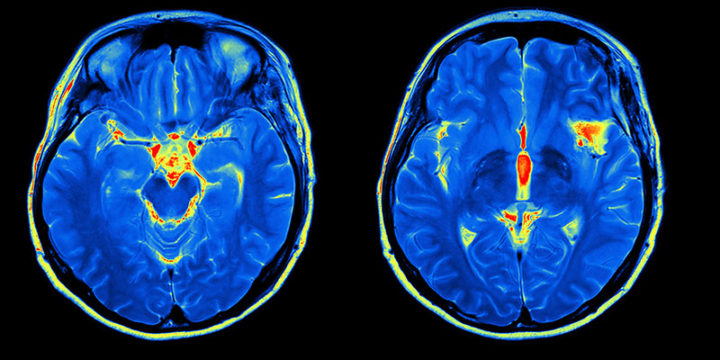

E’ uno strumento di vitale importanza per la diagnosi di eventuali lesioni a livello dell’encefalo, sebbene la sua ‘’invenzione’’ sia stata principalmente volta alla ricerca sulla fisiologia del nostro sistema nervoso. Lo strumento che possiamo considerare primo antenato dei moderni sistemi di neuroimaging funzionale è ‘’La bilancia della circolazione umana’’, brevettato dall’italiano Angelo Mosso alla fine dell’800. Questo apparecchio venne considerato eccezionale perche permetteva di osservare la distribuzione del sangue durante le varie attività cognitive della persona, portando alla scoperta di alcune aree preposte a determinate funzioni. I metodi utilizzati più comunemente includono la Tomografia ad emissione di positroni (PET), la Risonanza magnetica funzionale (fMRI), l’Elettroencefalogramma multicanale (EEG), la SPECT, la Magnetoencefalografia (MEG) e la spettroscopia funzionale nel vicino infrarosso (fNIRS). La PET e la risonanza magnetica funzionale hanno come principio di fondo lo stesso che Mosso aveva applicato nell’800, consentendoci quindi di avere un’ottima visione di insieme su come il sangue viene distribuito nelle nostre strutture encefaliche in base alle diverse stimolazioni o attività di tipo cognitivo. L’aumento di flusso ematico in una data zona del nostro telencefalo, per esempio, ci fa capire che, in quella circostanza, quella determinata area è più attiva rispetto alle altre. Nel meccanismo della visione, il lobo occipitale del telencefalo risulta più attivo rispetto al temporale, cosa che invece non si realizza quando ascoltiamo una canzone, per esempio. Questo consente di avere una vera e propria mappatura delle varie funzioni cerebrali e non solo. Nonostante tutto, però, ci sono alcune aree del nostro cervello ancora remote e quasi del tutto inesplorate.

Grazie alle tecniche di neuroimaging, sono state scoperte delle aree molto specializzate in determinate funzioni, come parlare, comprendere, ascoltare, integrare informazioni e via discorrendo. Non bisogna pensare, però, che una data funzione possa essere localizzata solo in un lobo specifico del nostre telencefalo, perchè è risultato di connessioni che, nella stragrande maggioranza dei casi, implicano diverse zone, anche esterne al cervello. Quello che noi chiamiamo comunemente cervello, in realtà è costituito da due porzioni: il diencefalo ( talamo, subtalama, ipotalamo ed epitalamo) e il telencefalo con i suoi due emisferi tenuti assieme e connessi dal corpo calloso. Il telencefalo presenta le famose circonvoluzioni che, spesso, portano a compararlo ad una noce sgusciata. Quello che noi osserviamo dall’esterno, è la corteccia, ovvero una struttura di sostanza grigia ( corpi dei neuroni con nucleo e organelli) che presenta diverse aree associative, 24 per la precisione. Le aree associative sono delle zone principalmente preposte ad adempiere determinate funzioni, come garantire la visione, il riconoscimento dei volti, l’apprendimento e la comprensione di parole creando delle connessioni tra dei centri di ricezione di informazioni (dette aree sensitive) e centri di innesco di risposta (aree motorie). Inizialmente, si pensava che queste aree avessero due funzioni soltanto, ovvero integrazioni di informazioni pervenute mediante specifiche afferenze dalle aree sensitive primarie e di ‘’connetterle’’ con le aree effettrici per ottenere una risposta . In realtà, c’è ancora molto da capire e da scoprire sulle effettive funzioni della nostra corteccia.

Per spiegare meglio i concetti espressi sopra, facciamo qualche esempio di area associativa. L’area associativa posteriore è localizzata nella zona a ridosso dei lobi occipitale, temporale e parietale. Integra diverse informazioni ed è principalmente implicata nell’attenzione, nel linguaggio, nel riconoscimento della propria persona, dell’ambiente e partecipa all’organizzazione di movimenti complessi. L’area associativa limbica è localizzata proprio sulle facce mediali dei due emisferi telencefalici ed è fondamentale per la memorizzazione di tipo dichiarativo a lungo termine, ma è anche implicata nella gestione delle emozioni e del comportamento in risposta a quest’ultime. Tutte queste informazioni sul nostro cervello sono pervenute a noi grazie alle tecniche più recenti di neuroimaging, consentendoci di comprendere a fondo i meccanismi di integrazione, elaborazione e creazione dello stimolo effettore alla base delle principali funzioni fisiologiche. E’ strepitoso il modo in cui delle semplici connessioni tra cellule specializzate possano creare una fitta rete di segnali che attivano vie preposte a determinati scopi, come il movimento, la memoria, il comportamento emotivo. Ancora molte cose sembrano quasi impossibili da comprendere, ma prima o poi riusciremo a decifrarle e saremo in grado di ammirare la perfezione di cui siamo fatti!